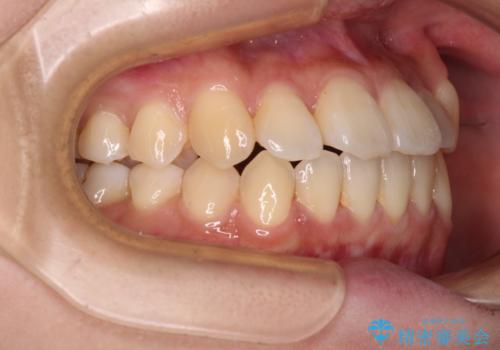

- 八重歯や前歯の捻転とクロスバイトが気になり、インビザラインによる矯正治療を希望して来院された患者様です。

上顎側切歯(上の真ん中から2番目の歯)が舌側転位している場合、無理して動かそうとすると歯髄壊死を起こすリスクが高い印象があります。

インビザライン単体でも治療は可能ですが、安全策としてインビザラインで歯列を移動する前に上顎前歯をワイヤー矯正で整え、その後上下歯列をインビザラインにて矯正治療を行うこととしました。

舌側転位している側切歯特有の、切縁の位置が不揃いであったり、根元が内側に引っ込んだ状態であったりという、インビザライン独特の仕上がりになることなく、きれいに整った歯列とすることができました。